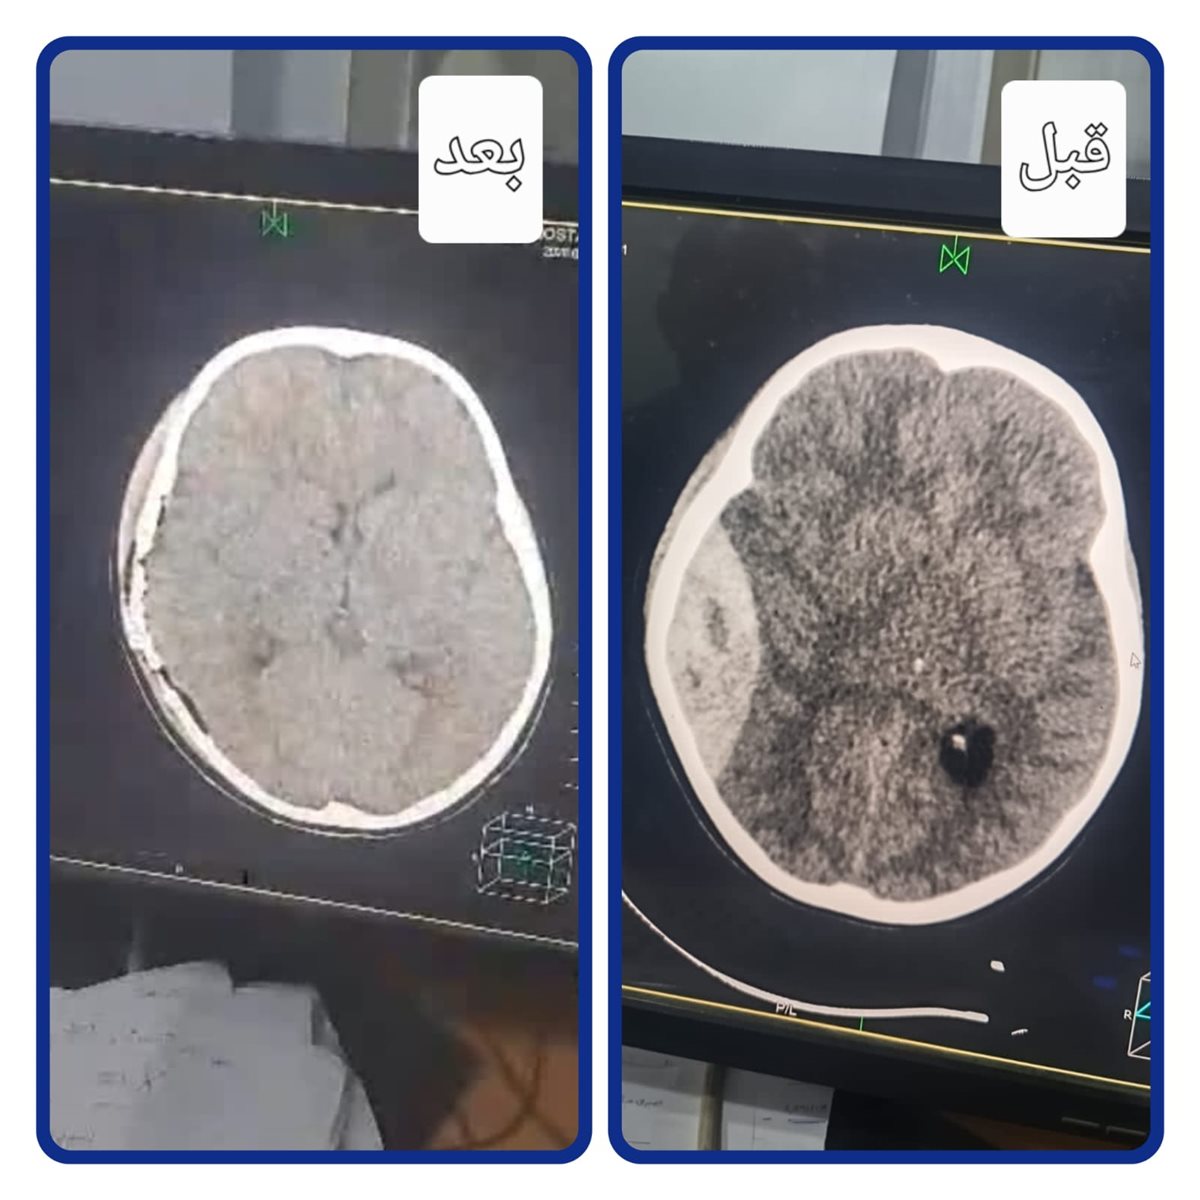

استقبلت مستشفى اجا المركزى طفل تعرض لإصابة خطيرة بالمخ إثر حادث تصادم بدراجة نارية والحالة تعاني من نزيف فوق الأم الجافية مصحوبًا بتدهور شديد في درجة الوعي والإدراك، وعلى الفور تم التعامل مع الحالة بشكل عاجل، حيث جرى إدخال الطفل إلى غرفة العمليات وإجراء جراحة دقيقة لتفريغ النزيف بالمخ، مع حجزه بالعناية المركزة لمتابعة حالته الصحية.

وخلال المتابعة الدقيقة، أظهرت الأشعة المقطعية وجود تجمع دموي آخر، ما استدعى التدخل الجراحي العاجل للمرة الثانية خلال أقل من 24 ساعة، حيث تمكن الفريق الطبي من إجراء العملية بنجاح، مع تفريغ النزيف والسيطرة على مصدره، ما ساهم في تحسن الحالة بشكل ملحوظ، واستعادة المريض لدرجة وعي كاملة (15/15)، قبل أن يتماثل للشفاء ويغادر المستشفى بحالة جيدة.